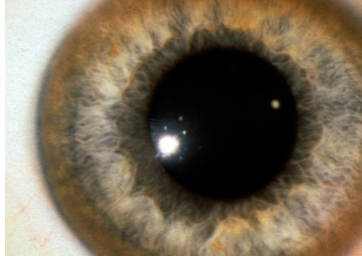

A 26 years old female presented with dystonia. O/E is found to have ascites due to portal hypertension & asymptomatic golden brown rings around the corneo-scleral junction (limbus) of the eyes as shown

-

What you see in Pic ? Kayser Fleischer

Diagnosis?: Wilson’s Disease